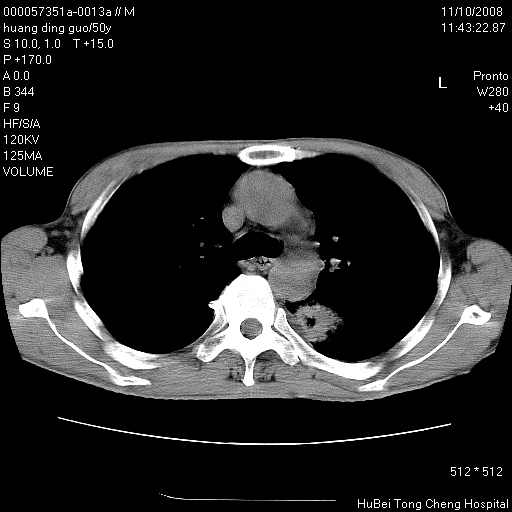

患者 男,50岁。左侧腰背部疼痛3月余,伴消瘦。平素健康,无传染病史。

胸部ct轴位平扫(层厚10mm,螺距1.5,重建间隔10mm),图像如下:

左肺下叶背段有一厚壁空洞,外壁呈锯齿状伴毛刺改变。空洞相邻胸膜有牵拉改变。左肺下叶血管支气管束不规则增粗,小叶间隔增厚。胸椎骨质破坏。考虑左肺下叶周围型肺癌伴左肺下叶癌性淋巴管炎、胸椎转移。

左肺下叶背段有一厚壁空洞,外壁呈锯齿状伴毛刺改变。空洞相邻胸膜有牵拉改变。左肺下叶血管支气管束不规则增粗,小叶间隔增厚。胸椎骨质破坏。考虑左肺下叶周围型肺癌伴阻塞性肺炎、胸椎转移。其他待排

左肺下叶背段有一厚壁空洞,内壁不规则,外壁呈锯齿状伴毛刺改变。空洞相邻胸膜有牵拉改变。周围呈絮状炎性改变,左肺下叶血管支气管束不规则增粗,小叶间隔增厚。胸椎骨质破坏。考虑左肺下叶周围型肺癌伴左肺下叶阻塞性肺炎、胸椎转移。